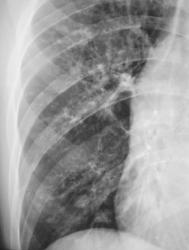

Иллюстрация 2. Слева определяется субтотальное снижение прозрачности легочного поля за счет наличия значительных размеров паракостального осумкованного выпота, имеющего чёткий и ровный контур. На фоне инфильтративно измененной легочной ткани в верхнем, среднем и нижнем легочных полях четко определяются две структуры — просветления с горизонтальными уровнями жидкости. Слева купол диафрагмы подтянут, фиксирован. Тень средостения резко смещена вправо.